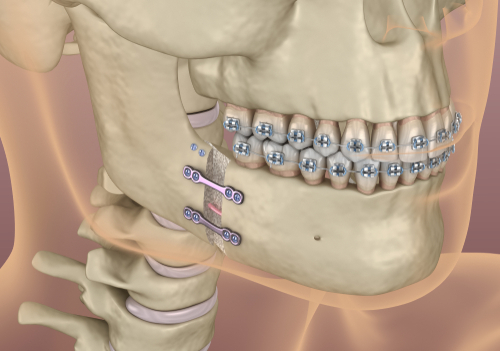

כירורגיה אורתוגנטית

הכירורגיה האורתוגנטית זו שיטה טיפולית הנעזרת בניתוח לצורך תיקון היחס הבין לסתי. כאשר לסת אחת בולטת מאוד לעומת השניה או כאשר לסת אחת צרה מאוד לעומת השניה.